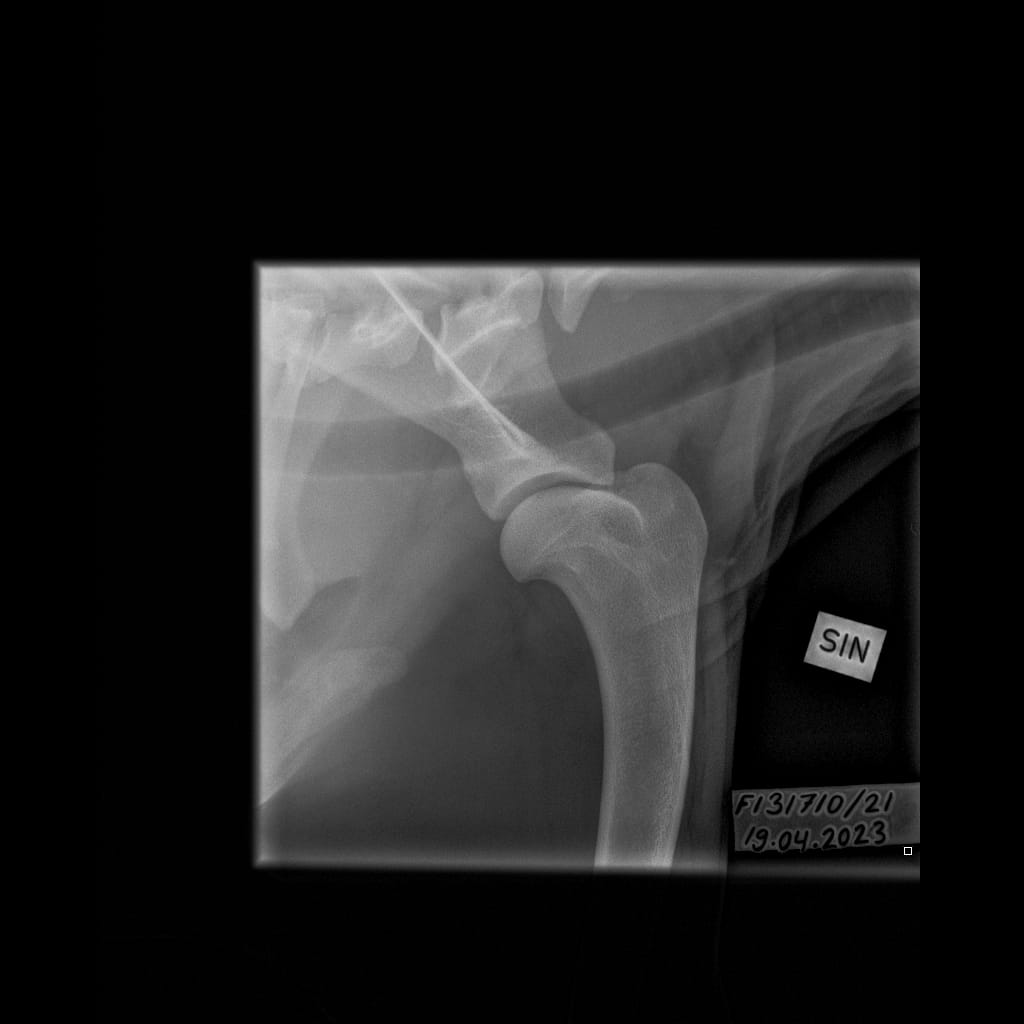

Topi’s OCD

Eturaajat -Olkanivel ML -6.11.2023-16_02_18-265 (1)